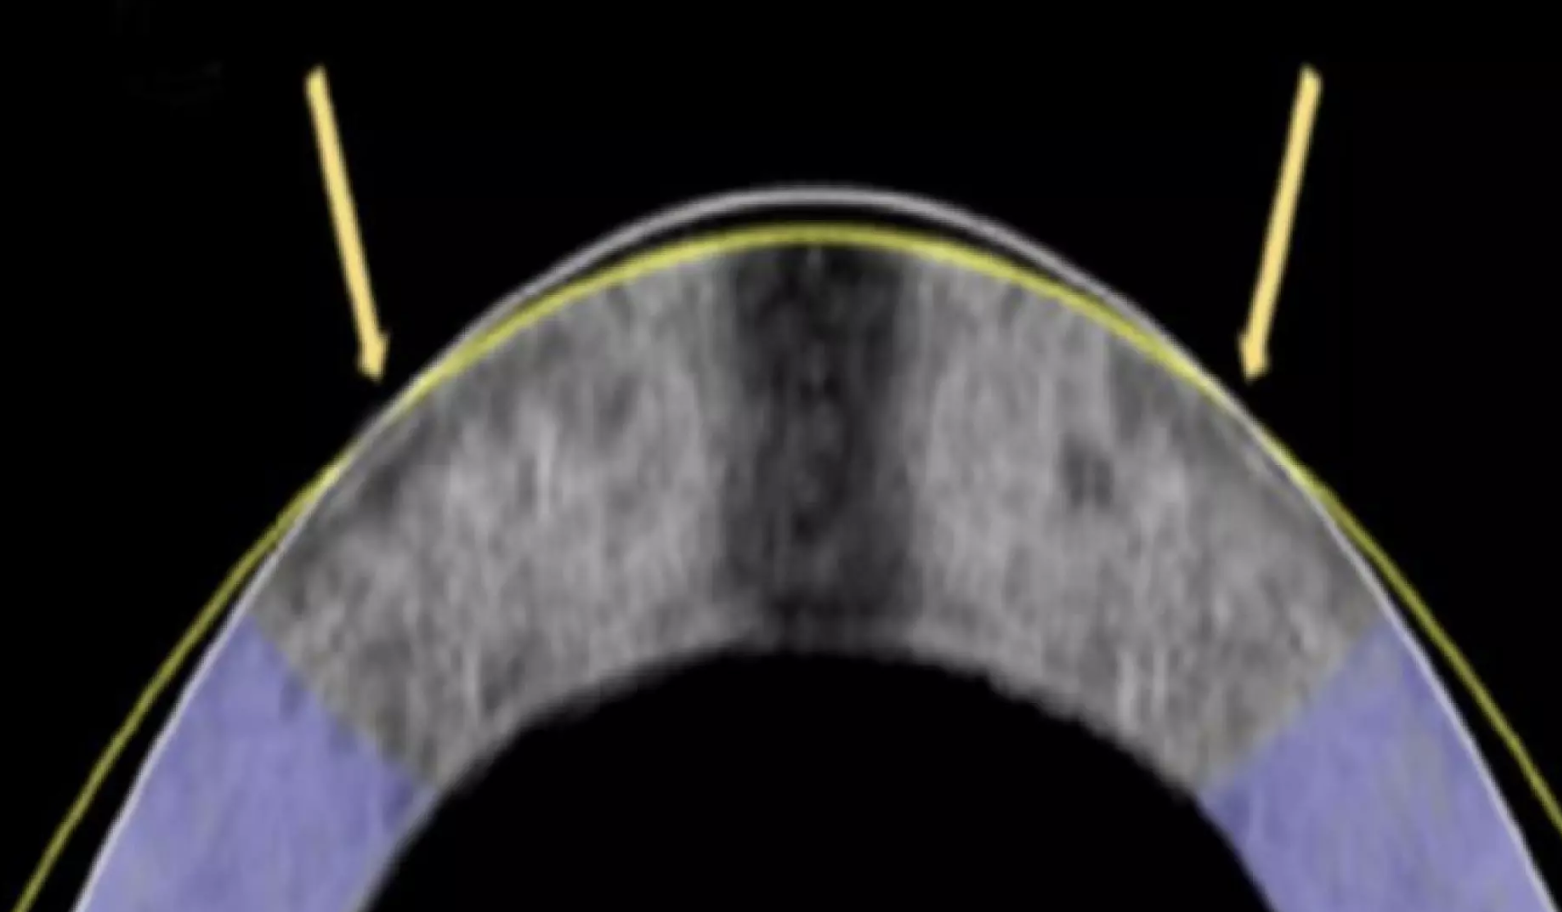

Сухость, эффект от фар машин ночью типа пикрил - были и есть, хоть и не такие ярко выраженные, как некоторые пишут. Симптомы ослабели спустя где-то полгода, но полностью так до сих пор и не прошли, регулярно капаю увлажняющие капли, слежу за тем что бы пить достаточно воды, и стараюсь делать перерывы, но всё равно сухость остаётся.